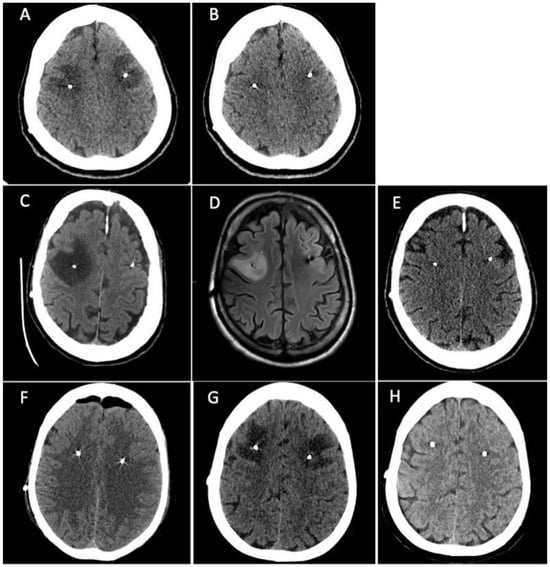

3.1. Patient 1

3.2. Patient 2

3.3. Patient 3